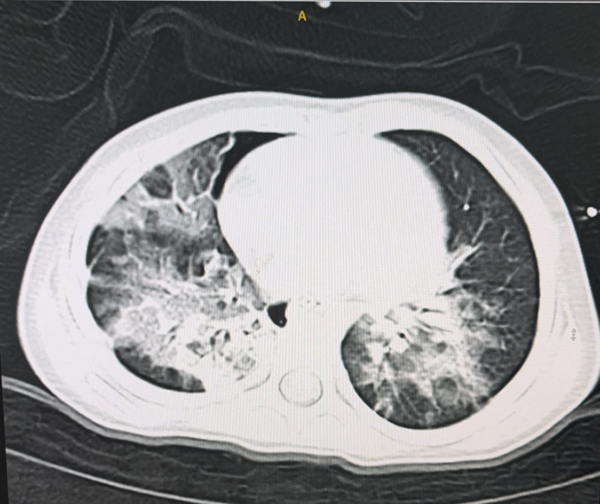

患儿入院时的胸部CT

入院时,欣欣呈昏迷状态,高热,在无创呼吸机辅助呼吸下仍有呼吸困难,经皮氧饱和度仅为88%,四肢肌力均0级,腱反射消失。小儿重症医学科负责人靳有鹏教授带领团队对欣欣的病情进行了全面评估,先给予气管插管、呼吸机辅助呼吸,并积极完善相关辅助检查。颅脑及脊髓MR检查提示:双侧侧脑室周围、放射冠、基底节区、脑干及皮层下见多发斑点状、斑片状异常信号,脊髓全长肿胀。呼吸道病原学检测发现腺病毒阳性。经与小儿神经科会诊讨论后,明确诊断为急性播散性脑脊髓炎合并腺病毒及耐药支原体感染、呼吸衰竭。神经系统损伤累及范围很广,包括脑内大片区域及全脊髓,同时欣欣还存在腺病毒及耐药支原体感染。单纯腺病毒感染病死率极高,合并耐药支原体感染后,治疗难度极大,预后极其不乐观。

面对重重困难,靳有鹏教授带团队迎难而上,经过综合评估和讨论后,确定了精准的治疗方案。一方面,患儿神经系统方面同时存在颅脑和脊髓的损伤:颅脑损伤范围广,影响到患儿的意识、自主呼吸功能;脊髓损伤累及到了全脊髓,患儿表现为颈部以下横贯性截瘫,颈部以下完全不能活动,感觉完全丧失,且存在尿储留。所以治疗方面需要给予大剂量丙球和激素,并且加用血浆置换,尽快清除患儿体内的致炎因子。护理团队则定时为其翻身,防止压疮发生。另一方面,欣欣的呼吸中枢及呼吸肌均受累,不能自主呼吸,且无咳嗽反射,前期肺部存在腺病毒和支原体感染,后期肺部先后合并了金黄色葡萄球菌、鲍曼不动杆菌、纹带棒状杆菌等细菌感染。需要护理人员精心照料,帮助患儿排痰,同时多次进行床旁纤支镜灌洗治疗,并依据病原学变化,及时调整抗感染治疗方案。